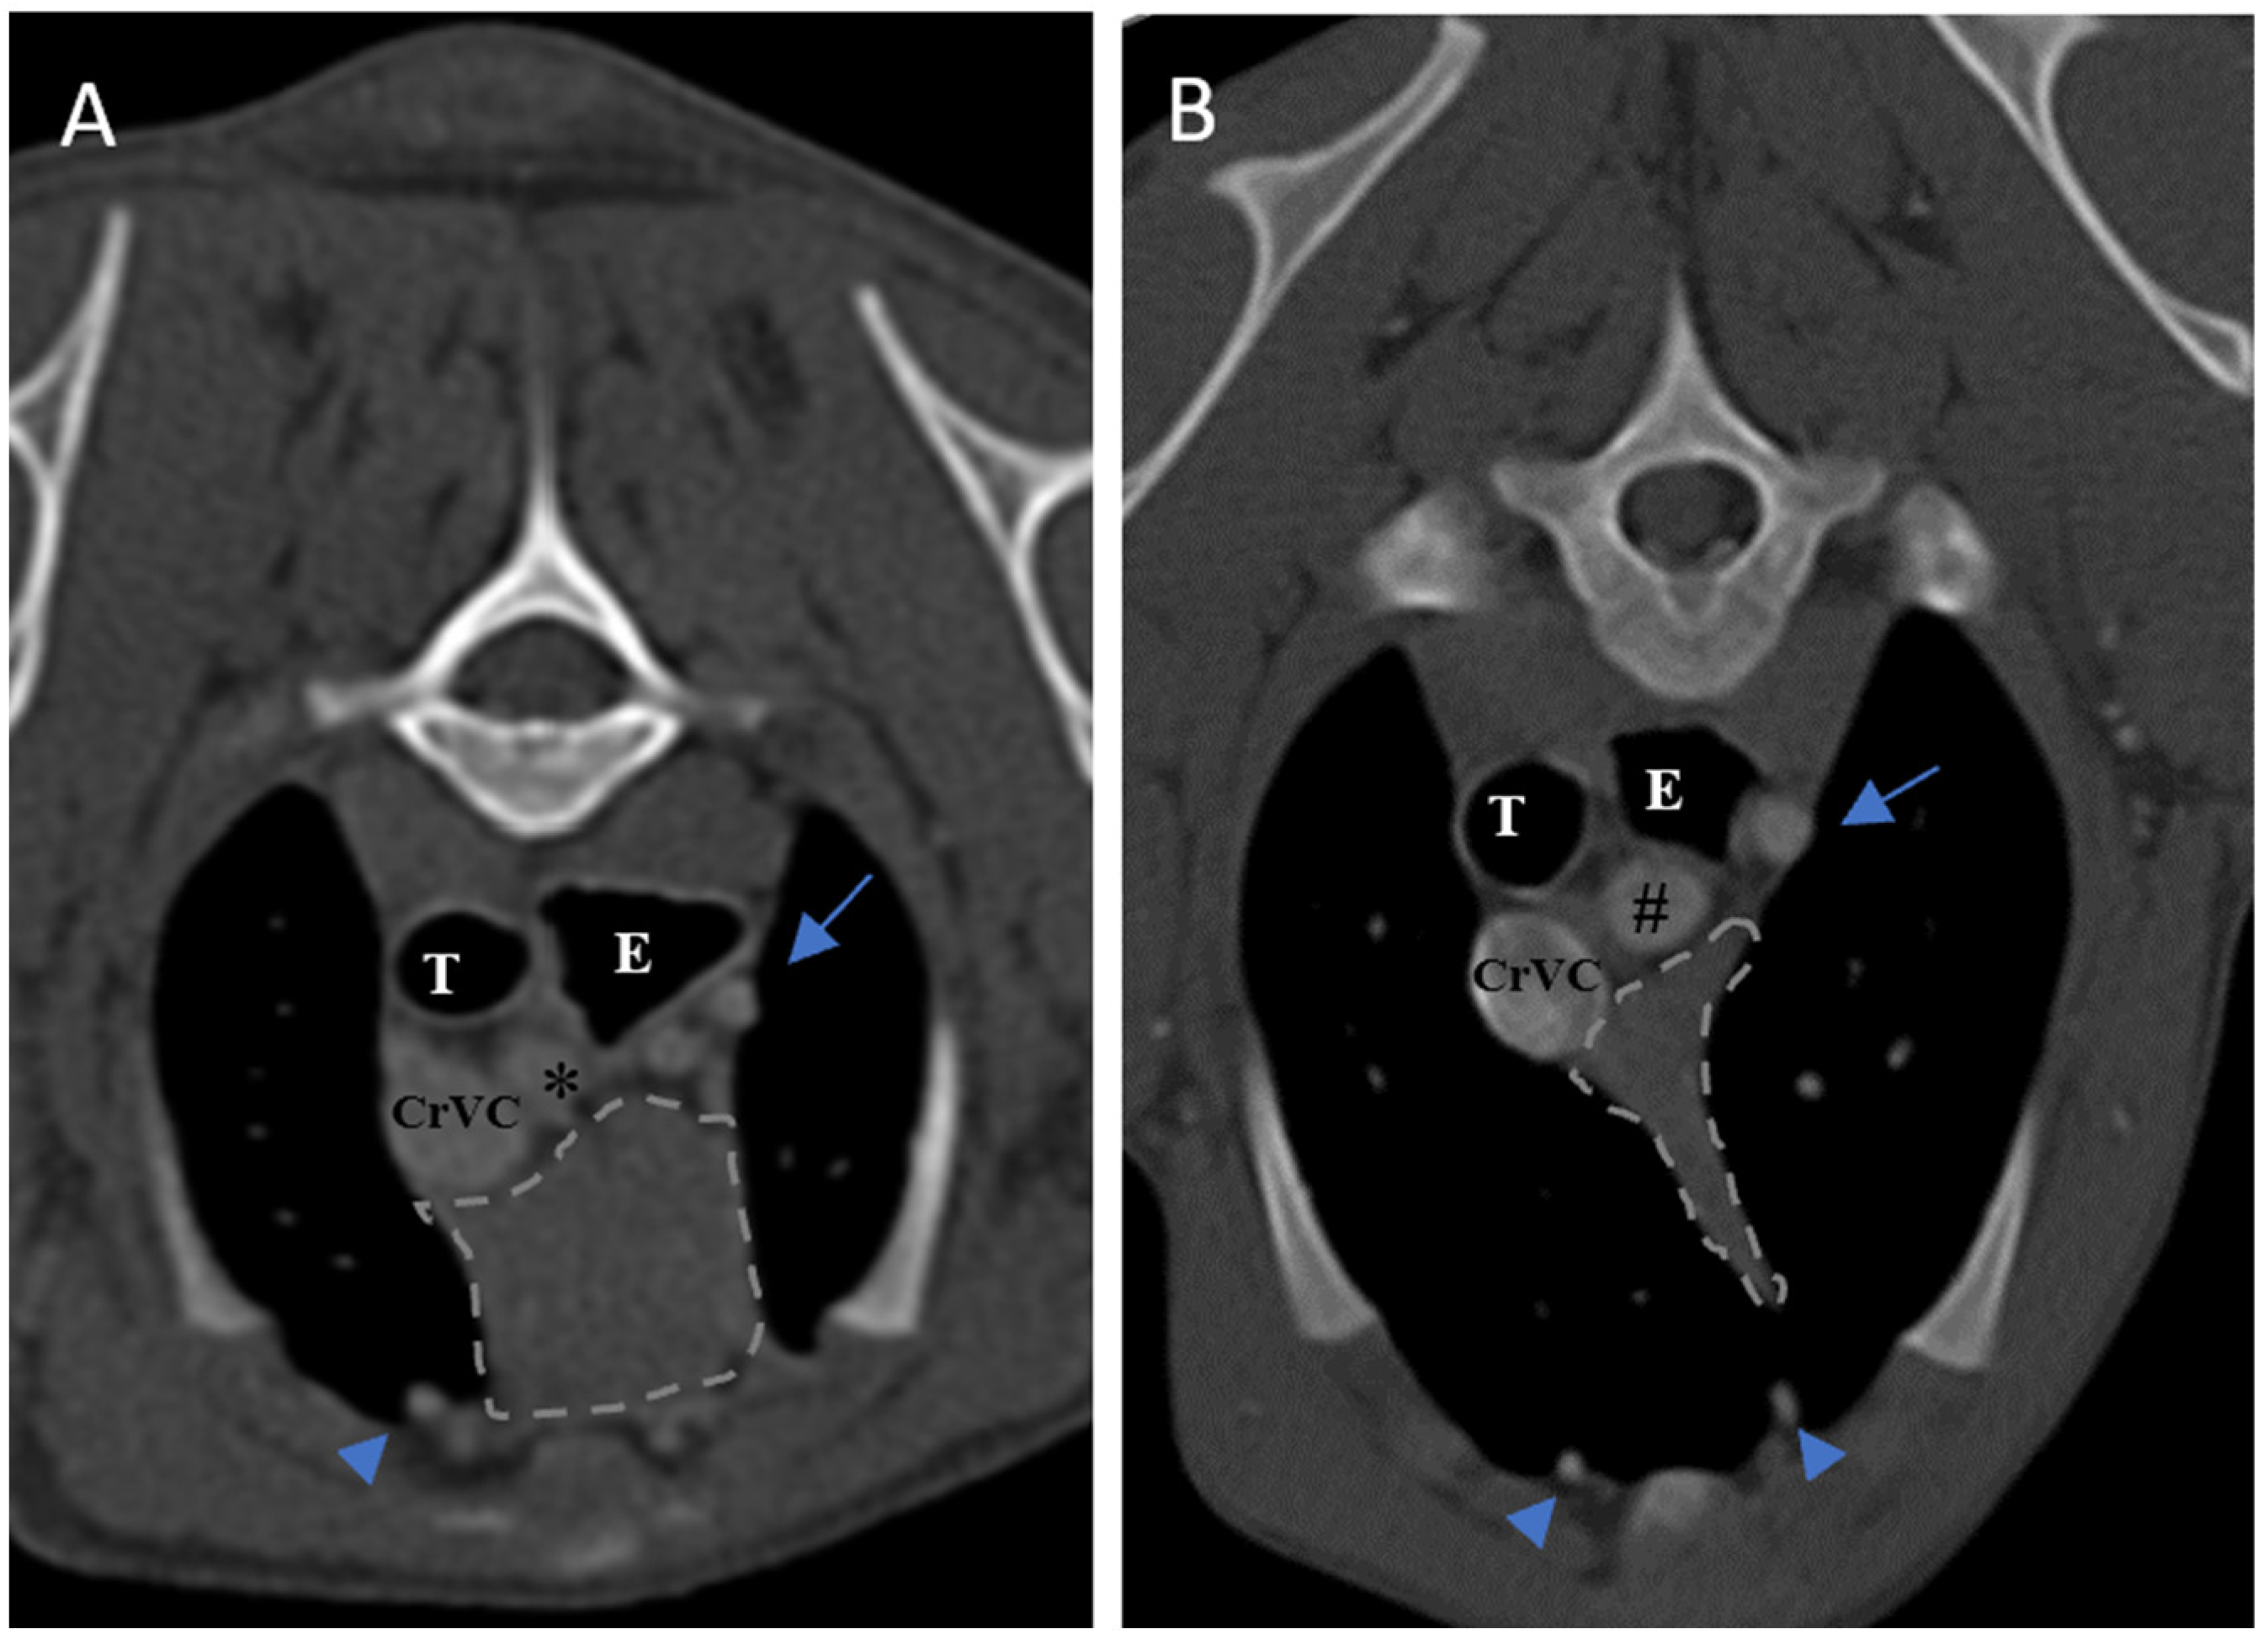

The size of the thymus was also measured in transverse and dorsal images. The maximum height (TH) and diameter (TD) in transverse images and maximum diameter (DD) and length (DL) in the dorsal views were measured (Figure 2), as well as thymic volume (TV) in all groups. These indices were measured in the area related to the mediastinal fat at the normal location of the thymus for patients with a completely fatty replacement of the thymus (grade 0). All measurements were performed in contrast-enhanced examinations. To normalize the thickness of the thymus in the transverse view, the height of the second thoracic vertebra midbody was measured and the ratio was calculated. The correlation between thymic size and grade with the body fat content was evaluated by measuring the thickness of subcutaneous fat in the dorsal aspect of the T4 spinous process (Figure 3). Subjective characteristics such as predominant deviation of the thymus to left, midline or right position, the thymic shape (wedge shaped, rectangular shaped, or linear shaped), and the thymic contour (convex and concave) were also evaluated. For patients with fatty degeneration, these characteristics were analyzed in mediastinal fat at the location of the previous thymus. Evaluation of thymic size, volume, attenuation, and grade was performed twice by a single person within a week, and the mean value of the first and second measurements for numerical data and the second results for thymic grading were reported.

Figure 2. Measurement of maximum height and diameter of thymus in transverse section (A) and maximum length and diameter in dorsal section (B) in post-contrast CT scans. The grey double arrows show the regions of measurement. Both figures belong to a five-month-old female shih Tzu. The thymus is grade 3, rectangular shaped with one convex border and midline position. L: lung, T: trachea, E: esophagus (which is dilated due to general anesthesia), CrVC: cranial vena cava, H: heart, black asterisk: right subclavian artery, shorter blue arrow: left common carotid artery, and longer blue arrow: left subclavian artery.